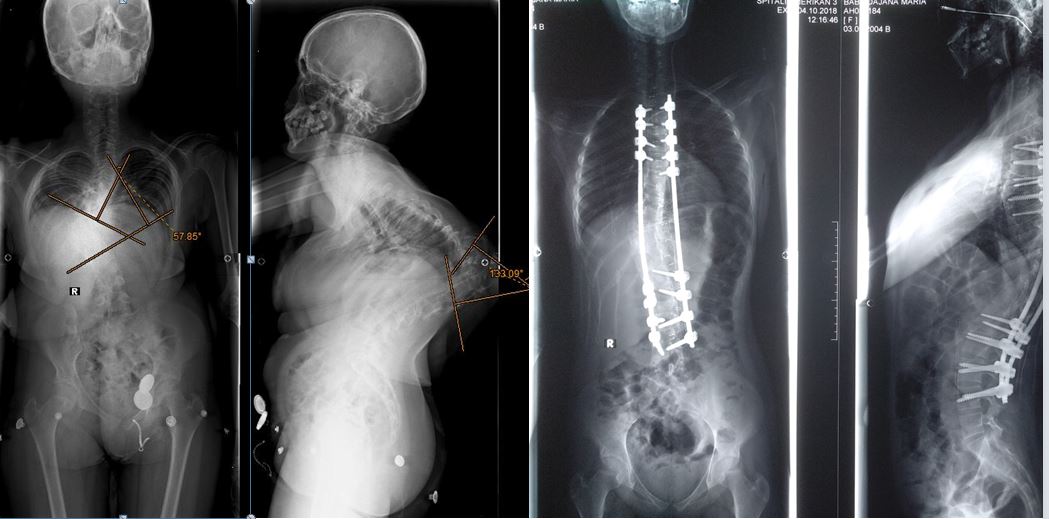

Krahasimi i ekzaminive radiologjike para dhe 8 ditë pas ndërhyrjes tregoi një ndryshim radikal. Jo vetëm që deformimi është korrigjuar, por në të njëjtën kohë tumori është hequr. Edhe në aspektin estetik, trupi i pacientes së re ka një pamje të rregullt.